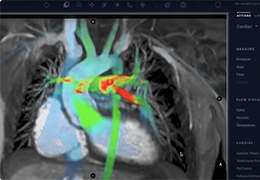

工作流智能。

在这里,先进的智能功能自动执行手动任务和工作流程步骤,以简化流程,提高技术人员工作效率,节省时间和金钱,并增强患者护理。

自动化设备定位和患者姿势确认可优化放射科技师的效率并加快工作流程。

自动技术选择可改善影像一致性并支持辐射剂量控制。

通过任务自动化功能改进感染控制,使放射科技师不再与潜在感染患者直接接触。